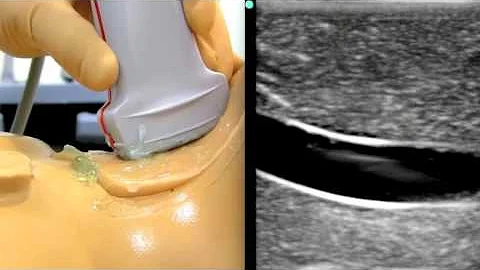

Ultrasound For Needle Guidance Using The In Plane Approach

GCUS Instructor James Mateer, MD explains how to use the in-plane approach with ultrasound for needle guidance.